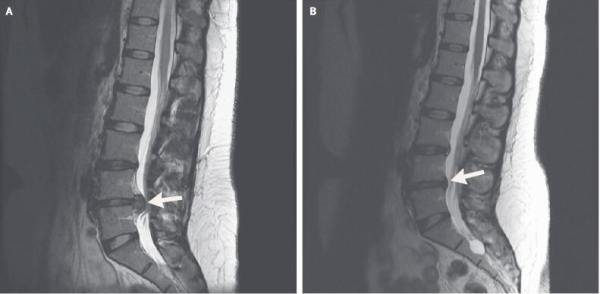

以下是该患者5个月前后两次MRI(核磁共振)的对比图:

很明显,突出的腰椎间盘有所回纳。